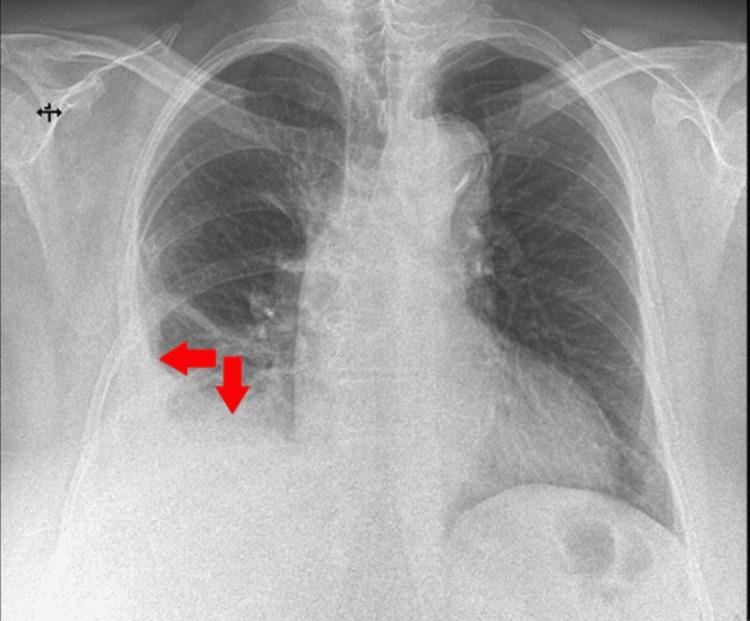

We present the clinical case of a 58-year-old female patient, a smoker with occupational exposure to respiratory toxins, who was admitted to our clinic following evaluation in an emergency department, where she was diagnosed with a moderate right pleural effusion. Upon admission, the patient exhibited respiratory symptoms, including progressive dyspnea with a moderate exertion threshold, right posterior pleuritic chest pain radiating anteriorly, occasional episodes of low-grade fever, and persistent febrile symptoms lasting approximately two weeks. In this clinical context, the diagnostic process was guided by the presence of right pleural effusion syndrome, which was refractory to conservative medical therapy. This necessitated a careful and stepwise expansion of investigations, ultimately leading to the diagnosis of malignant pleural mesothelioma. This case underscores the diagnostic challenges posed by pleural effusion, the necessity of adhering to the diagnostic algorithm, and the critical role of the multidisciplinary team. The diagnostic approach, often complex and challenging, necessitates a multidimensional strategy that integrates the correlation and synthesis of data obtained through anamnesis, alongside advanced diagnostic procedures such as pleural biopsy, which remains the gold standard. This comprehensive process is essential for formulating a diagnostic suspicion, with the final diagnosis intended to be one of exclusion.

摘要

我们介绍了一名58岁女性患者的临床病例,该患者有吸烟史且职业性接触呼吸道毒素,在急诊科评估后被收治入我院,在急诊科她被诊断为中度右侧胸腔积液。入院时,患者出现呼吸道症状,包括中度活动量时逐渐加重的呼吸困难、放射至前胸的右侧后胸膜炎性胸痛、偶尔的低热发作以及持续约两周的发热症状。在此临床背景下,诊断过程以右侧胸腔积液综合征的存在为指导,该综合征对保守药物治疗无效。这就需要谨慎且逐步地扩大检查范围,最终确诊为恶性胸膜间皮瘤。该病例强调了胸腔积液带来的诊断挑战、遵循诊断流程的必要性以及多学科团队的关键作用。诊断方法通常复杂且具有挑战性,需要一种多维策略,将通过问诊获得的数据的相关性和综合分析与先进的诊断程序(如胸膜活检,其仍是金标准)相结合。这一全面的过程对于形成诊断怀疑至关重要,最终诊断旨在排除其他可能。